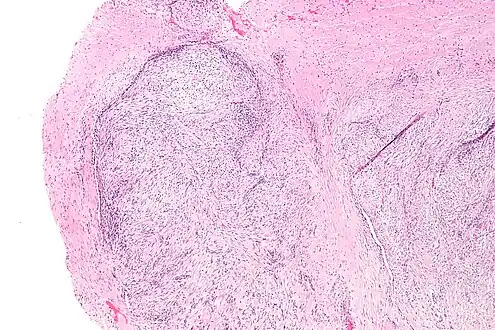

The microscopic histopathology of hematoxylin and eosin stained nodular fasciitis tumors (see above and three below figures) consists of spindle-shaped myofibroblastic cells (i.e. cells with features of smooth muscle cells and fibroblasts.).[9] These cells are in a myxoid (i.e. more blue or purple compared to normal connective tissue because of excessive uptake of the hematoxylin stain) or a collagenous (high content of collagen fibers) tissue background. The neoplastic myofibroblasts are arranged in whorls and/or short bundles. These cells may show high rates of replicating as judged by their mitotic index but these mitoses are normal in appearance. The tumor tissues often contain red blood cells, lymphocytes and giant osteoclast-like giant cells and may contain sites of bone-like tissue.[11] NF is sometimes classified into three subtypes based on its predominant histopathological pattern: myxoid or reactive (type I), cellular (type II), and fibrous (type III).[5] These patterns appear related to the duration of the lesion with the myxoid variant tending to have the shortest duration and the cellular and fibrous variants tending to have progressively longer durations.[15]Immunohistochemical analyses indicate that the cells in NF usually express smooth muscle actin, muscle specific actin, and vimentin proteins but generally do not express CD34, S-100 protein, desmin, trypsin, factor VIII, F4/80 (also termed macrophage-specific antigen), or HLA-DR1 proteins.[11] Uncommonly, the cells in NF tumors also express the CD68 (a histiocyte-specific marker) protein.[5]

Low magnification